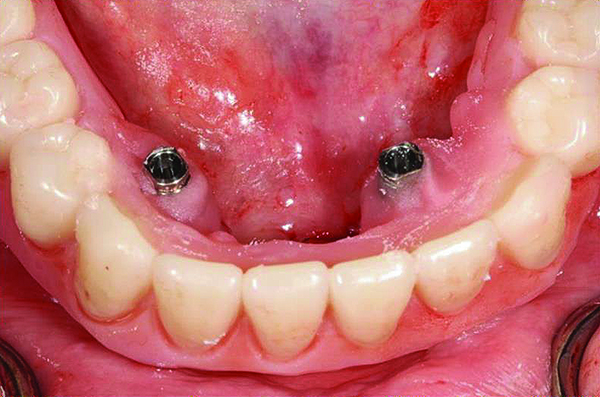

The patient’s intraoral condition.

Figure 18